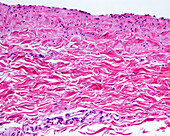

13416586 - Aorta tunica media and adventitia, light micrograph

12634941 - Aorta, tunica adventitia and media, LM

12634940 - Aorta, tunica adventitia and media, LM

12634939 - Aorta, tunica adventitia and media, LM